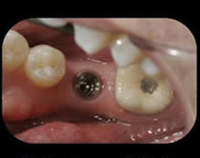

The patient came to us with the tooth already extracted (missing)

First step to surgically place the implant in the bone